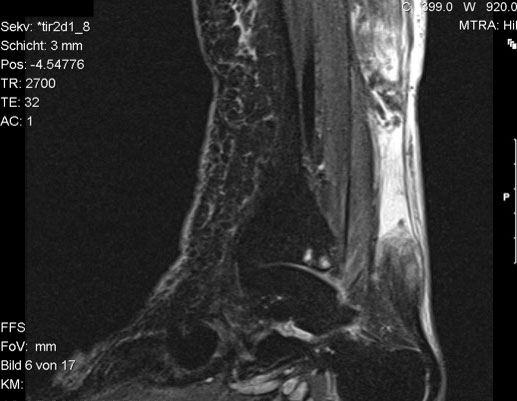

Der geübte Untersucher kann anhand des seitlichen Röntgenbildes die Diagnose einer Achillessehnenruptur stellen. Die Konturen des Kager-Dreiecks – gebildet von der ventralen Begrenzung der Achillessehne, der posterioren Tibiakante und der kranialen Kalkaneuskortikalis – verstreichen im Rupturfall (Kager 1939). Die MRT- Diagnostik spielt für die Primärdiagnostik der frischen Achillessehnenruptur eine untergeordnete Rolle und ist im Normalfall nicht notwendig. Anders verhält es sich bei den chronischen Rupturen. Hier ist die MRT ein wichtiges Diagnostikum insbesondere in Hinblick auf die Beurteilung der Sehnen- und Muskeldegeneration (Abb. 6).

Abbildung 6

Neben der strukturellen Wiederherstellung der Sehne ist die funktionelle Beurteilung des Muskels von entscheidender Bedeutung. Ist es bereits zu einer Degeneration der Muskeln gekommen, kann ein gutes funktionelles Ergebnis, trotz subtiler Sehnenrekonstruktion, nicht erreicht werden. Die Arbeitsgruppe um Hoffmann et al. 13 konnte in ihrer Arbeit zeigen, das es - ähnlich wie bei Patienten mit chronischen Supraspinatusrupturen - zu fettigen Degenerationen und Ödemen der Muskulatur kommt, die im MRT nachweisbar sind. Wir empfehlen die MRT- Untersuchung des gesamten Unterschenkels und nicht nur die rupturnahen Bereiche. Des Weiteren lässt die MRT eine Beurteilung der Degeneration der umliegenden Sehnenanteile zu. Die Computertomographie sollte nur in Ausnahmefällen zum Ausschluss von Begleitverletzungen (Abb. 7) durchgeführt werden und gibt uns sonst keinen weiteren Informationsgewinn.